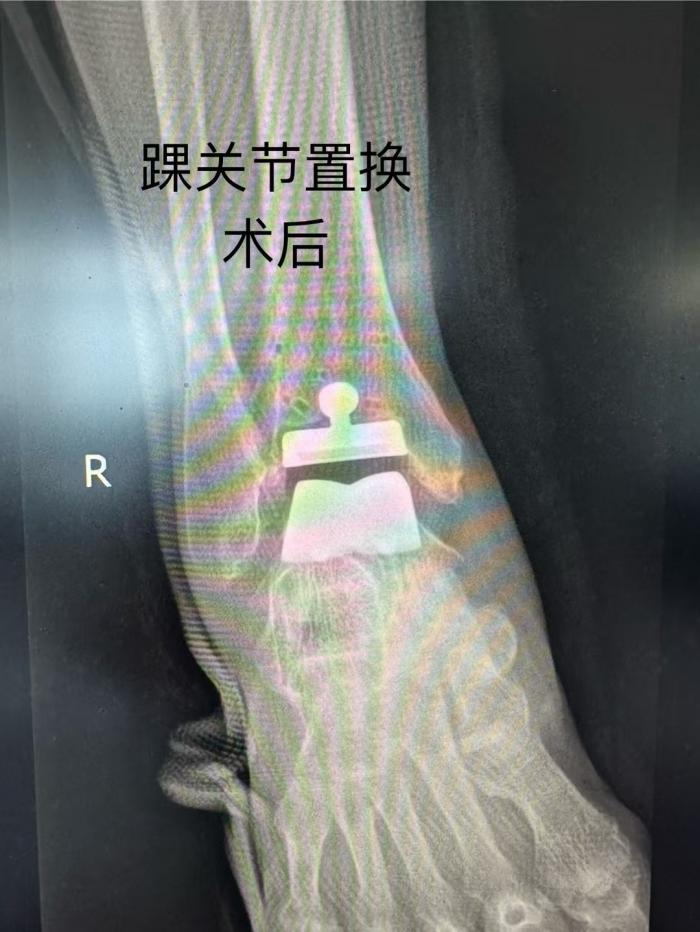

手术中,唐新文团队依托患者 CT 数据完成踝关节三维重建,通过3D打印技术 1:1 定制截骨导板,实现与骨性标志100% 贴合,将截骨误差严格控制在0.5mm以内(传统徒手操作误差达2-3mm)。借助导板精准引导,仅通过前侧7cm微创切口,便完成假体植入,手术耗时120分钟(较传统术式缩短60分钟),出血量控制在 100ml 以内,全程无需输血。术中通过导板预设的解剖参数优化,选择的第三代解剖型假体与骨骼接触面积增加 35%,配合仿生曲面设计及多孔涂层促进骨长入,显著降低术后松动风险。

术后,欧阳阿姨恢复情况良好。在麻醉苏醒后,她就在护士的指导下开始进行跖屈、背伸及直腿抬高训练。72 小时后,疼痛评分降至3分(VAS)。术后第5天,她已经能够使用助行器下地行走。欧阳阿姨开心地说:“现在脚踝轻松多了,也没那么痛了,就等着和老伴一起出院了。” 与此同时,同期接受人工股骨头置换术的老伴也恢复良好,预计本周可出院。

唐新文主任介绍,相较于传统踝关节融合术导致的功能丧失,3D 打印导板辅助置换术可保留25°关节活动度,降低邻近关节退变风险60% 以上。目前,湘南学院附属医院已实现髋、膝、踝、肩、肘等负重关节置换技术全覆盖,其中 3D 打印导板技术通过术前数字化模拟缩短年轻医师学习曲线,并将单例导板成本降至传统方法1/5,推动精准骨科技术向基层普及。